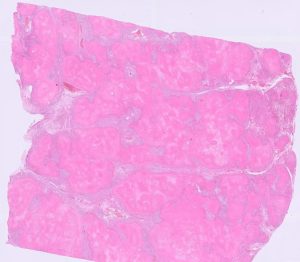

Figure 1: Lung tissue is near completely effaced by bright pink eosinophilic coagula (caseonecrotic material) in a calf with virulent Mycoplasmopsis bovis pneumonia.